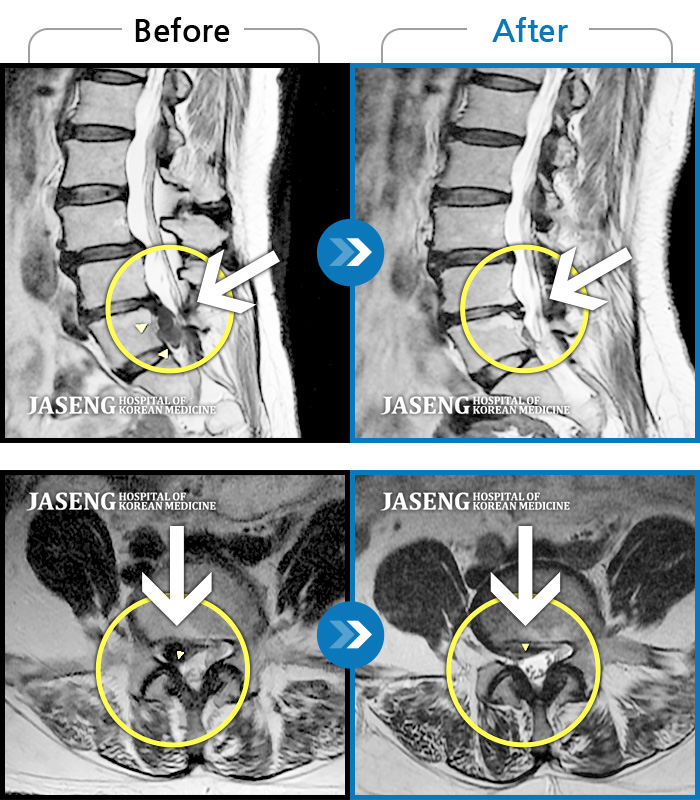

허리디스크

해운대 · 이상건 원장

허리통증 및 우측 하지 저림과 근력 저하

촬영시기

2018.02.05 ~ 2018.08.25

2019.01.04

조회수 5,050